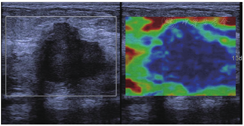

采用西门子ACUSON S3000型彩色多普勒超声诊断仪进行检查,采用9L4线阵高频探头,探头频率为9.0 MHz;检查时受检者取仰卧位,充分暴露乳房,首先采取灰阶与彩色多普勒超声检查,确定乳腺病灶位置、大小、回声、钙化、血供等信息,随后行施压式应变弹性成像:探头轻放于皮表,调节取样框感兴趣区大小为肿块的2~3倍,使之包括病灶全部及部分周围腺体组织,持稳探头,调整探头与皮肤的接触力度,使QF值稳定在60以上,弹性图显示较清晰的病灶轮廓时冻结,保存图像(见图1)。记录患者超声弹性成像评分,评分标准参考文献[7]。